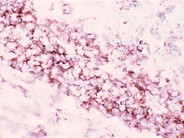

Immunoperoxidase stain of CD20+ B cells in monocytoid B cell hyperplasia.

Category: Reactive Marrow > Reactive changes